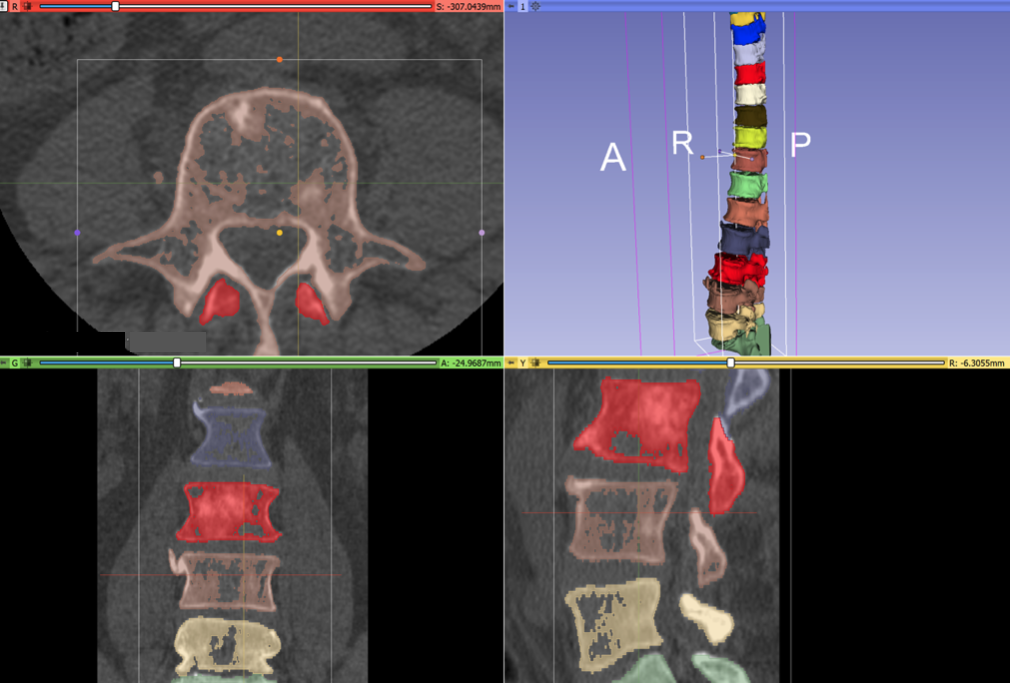

Because the bone in the spines is degraded from cancer, it is difficult to get a good segmentation. Here is the result of several hours of manual segmentation:

During the project week, we received consulting assistance on segmentation techniques from Andras Lasso and Rudolf Bumm. After Andras’ wrote us a post-processing script, the final result of registration is much better. These annotations can be used for neural net training: